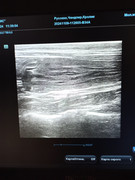

Сделали повторное узи 22.11. 2024 (первое было 09.11.2024). Высылаю фото и заключение.

Теперь ставят гидрометру и эндометрит. По мочевому мочекаменную.